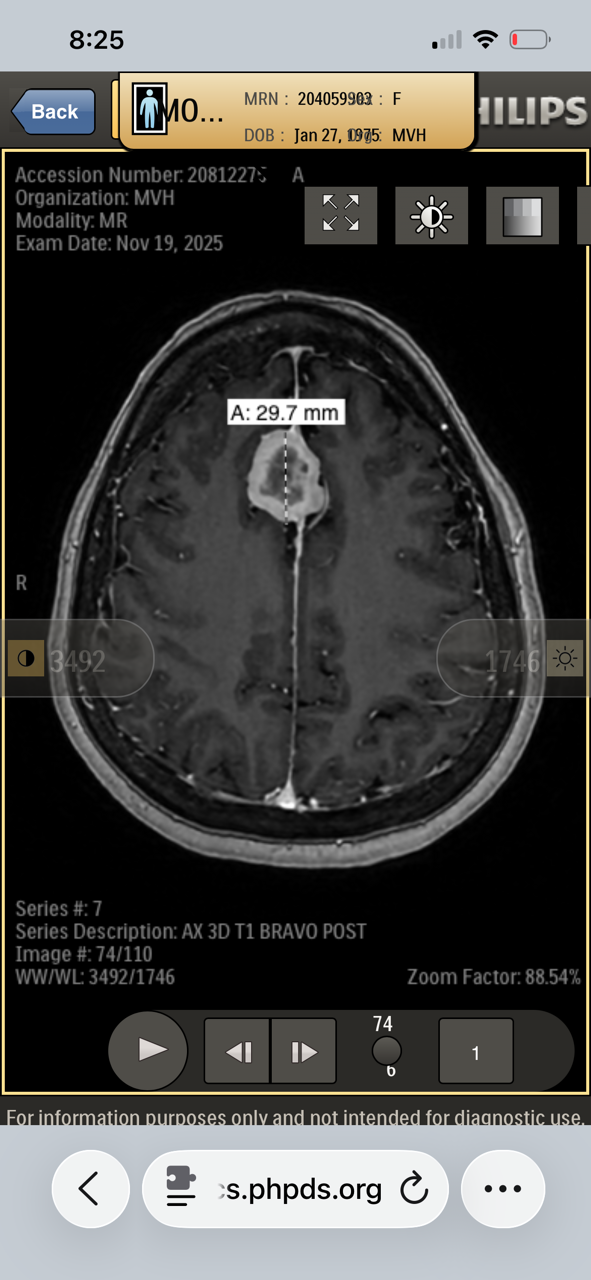

My name is Kory Burge and I'm raising funds for my mom, Angela Montgomery. She is a pediatric cancer survivor, prior pediatric oncology nurse and amazing mom and Mimi. When she was being treated for Stage III B Hodgkin’s Lymphoma in 1991 at the age of 16, they told my grandparents that the long-term concern is developing another cancer due to the harsh chemotherapy and radiation protocol, as well as heart and lung disease. As a parent, what choice do you have? Thirty-five years later, on November 18, 2025 after complaining for over three years to her doctors that something was desperately wrong and being denied an MRI, she convinced the ER doctor to do a CT on her head. They found two large brain tumors, one of which is pressing on and displacing her brain stem. She also has some on her spine, but they’re not sure how many yet. MRI of her entire spine is coming March 6th. This has kept her from working and she has used her retirement down to the penny, and now cannot work, nor support herself through this. Please donate if you can and share this with everyone you know.

The plan is to have the first surgery on March 10th to remove the brain tumor currently displacing her brainstem before it starts causing seizures. It will be 10-12 hours long, then 3 days in ICU and 3 days on the unit. The next will be to remove the one in her frontal lobe.